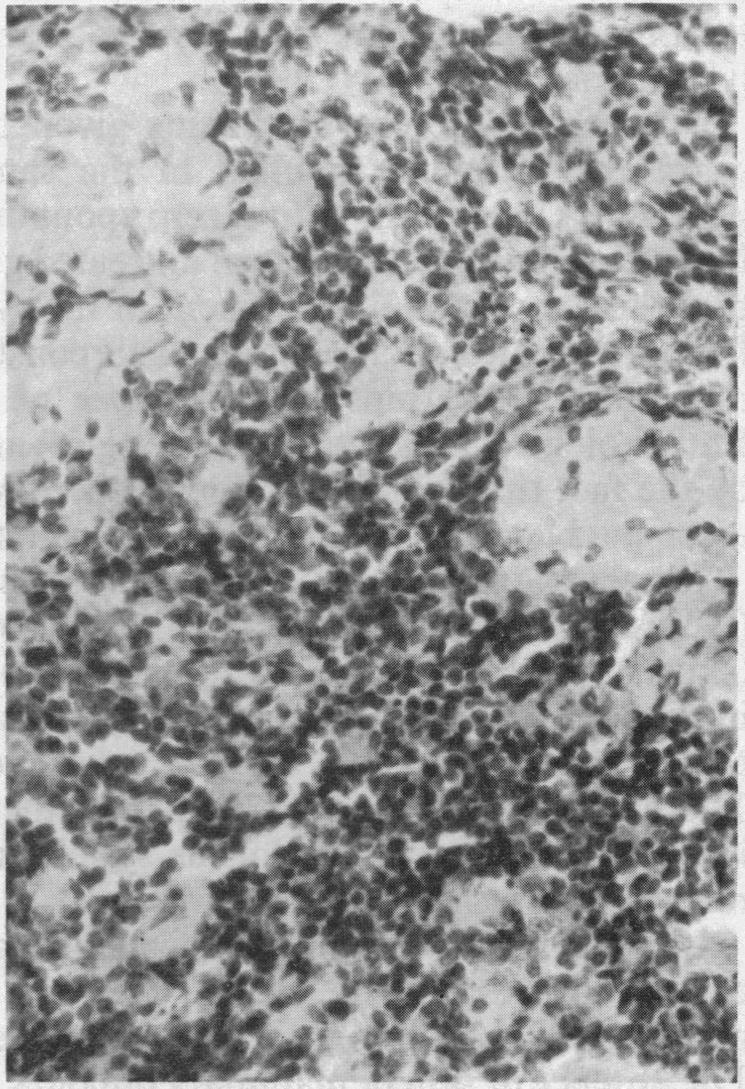

Previously, malignant lymphomas in mice have been found to be the late sequelae of the autologous transplantation of skin grafts pretreated with CO(2); these did not occur with grafts cultured in air alone. The clinical result in this autologous system reflects environmental differences in vitro (Goldsmith & Narvaez 1975). In the present study the syngeneic transplantation in BALB/c mice of lymph node tissue resulted in the late appearance of malignant lymphomas (48-69%), irrespective of the pretransplantation treatment of the grafts. Lymph node grafts were exposed to three different environments before transplantation into syngeneic hosts: (1) to culture in air (24 hours); (2) to culture in an atmosphere of 45% CO(2) in air (24 hours); (3) direct transplantation without in vitro exposure. Transplantation of these three groups of differently treated grafts was followed by the same clinical results in their recipients. These were: (1) The development of lymphoma whereas the spontaneous incidence was zero. (2) The proliferation of T-lymphocytes in the spleen; the incidence of this abnormality correlates with the lymphoma incidence. (3) A higher than normal occurence of immune-associated lesions (amyloidosis, interstitial nephritis and myocarditis). Both syngeneic and autologous transplantations may serve as animal models for the study of clinical malignant lymphoma.